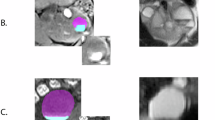

Transcriptomic analysis of male and female PCK kidney tissue

To further solidify sex differences contributing to the distinct male and female cystic profiles, we performed RNA-Seq analysis of renal cortex tissue from male and female PCK rats used for untargeted metabolomics. The full RNA-Seq dataset can be found in the Supplemental Data. The heatmap in Fig. 3A depicts the top up- and downregulated genes in females compared to males. After considering an adjusted p-value cutoff of 0.05 and log2 fold-change cutoff > 1, we found that 170 genes were upregulated and 198 were downregulated in females (Fig. 3B). Ingenuity Pathway Analysis (IPA) of this dataset revealed the top molecular and cellular functions associated with the differentially expressed genes (Fig. 3D), the top Gene Ontology (GO, Fig. 3E), and top Kyoto-Encyclopedia of Genes and Genomes (KEGG, Fig. 3F) pathways. Lastly, IPA identified a key signaling network involving the cystic fibrosis transmembrane regulator (CFTR), Notch, Rac, Vegf, S100A8, Hif1, and others whose expression and downstream activities are predicted to be less active (blue) in females (Fig. 3C). Increased circulating levels of VEGF37 and HIF-1a38 are associated with worsened PKD disease state, S100A8 upregulation is linked to receptor of advanced glycation end product (RAGE) signaling in inflammation and cystogenesis39, overexpression of Notch1 in renin-expressing cells resulted in development of fluid-filled cysts and increased proliferation markers40, and CFTR is a key chloride channel that may contribute to cyst growth41.

A Heatmap showing fold change differences for different animals. B Volcano plot of significantly up (orange) or down (blue) differentially expressed genes in females with a log2fold change (FC) > 1 and p-adjusted value < 0.05 as determined by differential expression analysis R-package DEseq2. C Signaling network demonstrating down-regulation of pathway-related genes including Vegf, Notch, Hif1a, and Cftr in females. Top Molecular and Cellular Functions (D), Gene Ontology Pathways (E), and KEGG Pathways (F) that are predicted to be different between male and female PCK kidney. N = 5 male and 5 female rats.